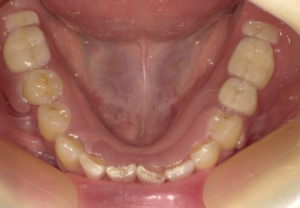

先日ミラクルデンチャーを入れられた方からお喜びの声をいただきました。

60代女性、以前まで保険の入れ歯を使用しており、

紛失したため、新しい義歯を作成することになりました。

そこでミラクルデンチャーをおすすめし、先日装着しました。